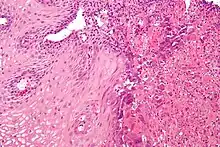

Reflux esophagitis

Although it usually assumed that inflammation from acid reflux is caused by the irritant action on the mucosa by hydrochloric acid, one study suggests that the pathogenesis of reflux esophagitis may be cytokine-mediated.[6]